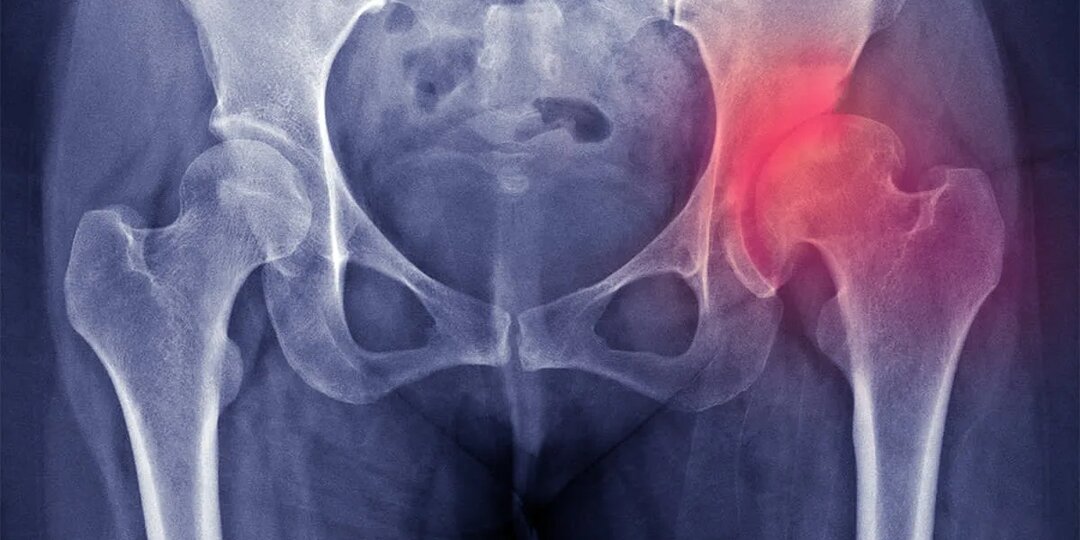

Коксартроз тазобедренного сустава: что делать, если боль в бедре мешает жить

Вы собираетесь выйти на улицу, но первый шаг отзывается острой болью в паху или сбоку бедра. Вы осторожно опираетесь на стену, делаете ещё один шаг — чуть легче, но дискомфорт остаётся. Через пару минут, кажется, проходит. Но к вечеру всё возвращается. Со временем вы начинаете избегать длительных прогулок, лестниц, даже походов в магазин. Ваш круг общения сужается, активность падает, а настроение — вместе с ней. Это может быть не просто «возрастное» недомогание, а коксартроз — постепенное разрушение тазобедренного сустава. И он может начаться не только после 60 лет, но и гораздо раньше. Многие привыкли думать: «Ну, суставы хрустят — с кем не бывает?» Но в случае с тазобедренным суставом это не просто дискомфорт. Здесь речь идёт о серьёзном процессе износа, который без внимания приводит к потере подвижности и снижению качества жизни. Однако есть и хорошая новость: даже при выраженном коксартрозе можно замедлить его развитие, снять боль и вернуть себе способность свободно двигаться. Гла